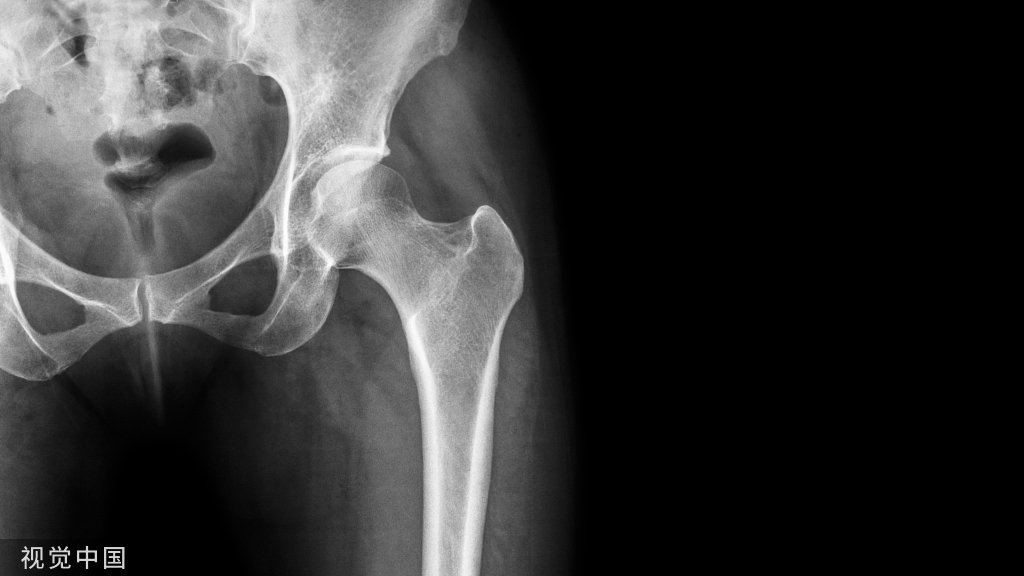

图4 一例89岁股骨粗隆间骨折患者,可见在正位片骨折显示良好,在侧位片上后区由于金属内植物遮挡,骨折部位显示不清。